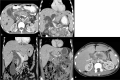

The purpose is to discuss abdominal tuberculosis mimicking malignancy involving the abdominal viscera. TB of the abdominal viscera is common, especially in countries where tuberculosis is endemic and in pockets of non-endemic countries. Diagnosis is challenging as clinical presentations are often non-specific. Tissue sampling may be necessary for definitive diagnosis. Awareness of the early and late disease imaging appearances of abdominal tuberculosis involving the viscera that can mimic malignancy can aid detecting TB, providing a differential diagnosis, assessing extent of spread, guiding biopsy, and evaluating response.